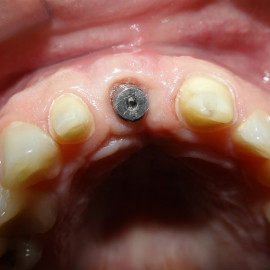

Po utracie zęba w przednim odcinku łuku zębowego należy zwrócić wzmożoną uwagę na aspekt estetyczny. Naczelnym przesłaniem odbudowy brakujących tkanek (anatomiczno-funkcjonalny kompleks tkanek: kość wyrostka zębodołowego + dziąsło + zęby) jest uzyskanie takiego wyniku, który jest najbliżej ideału, czyli takiej sytuacji jak gdyby nic się nie stało i w ogóle nie doszło do utraty zęba i tkanek około zębowych. Kluczem do sukcesu jest odtworzenie poprawnych stosunków anatomicznych: kość - dziąsło - ząb.

Korona protetyczna na implancie, funkcjonująca od roku 2003. Zdarzył się wypadek motocyklowy. Widzimy klucz do osiągnięcia sukcesu: mikrochirurgia i poprawna anatomiczna odbudowa tkanek. Tego nie zastąpi nawet najdroższy implant!

Pokazano etapową odbudowę brakujących tkanek, wraz z odbudową objętości i kształtu dziąsła.